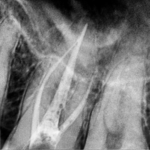

Digital X-Rays

Your X-Rays are now Faster in High Definition and Safe with us.

RCT

Get single visit Root Canal Therapies that saves your time and gives quick relief to your teeth.